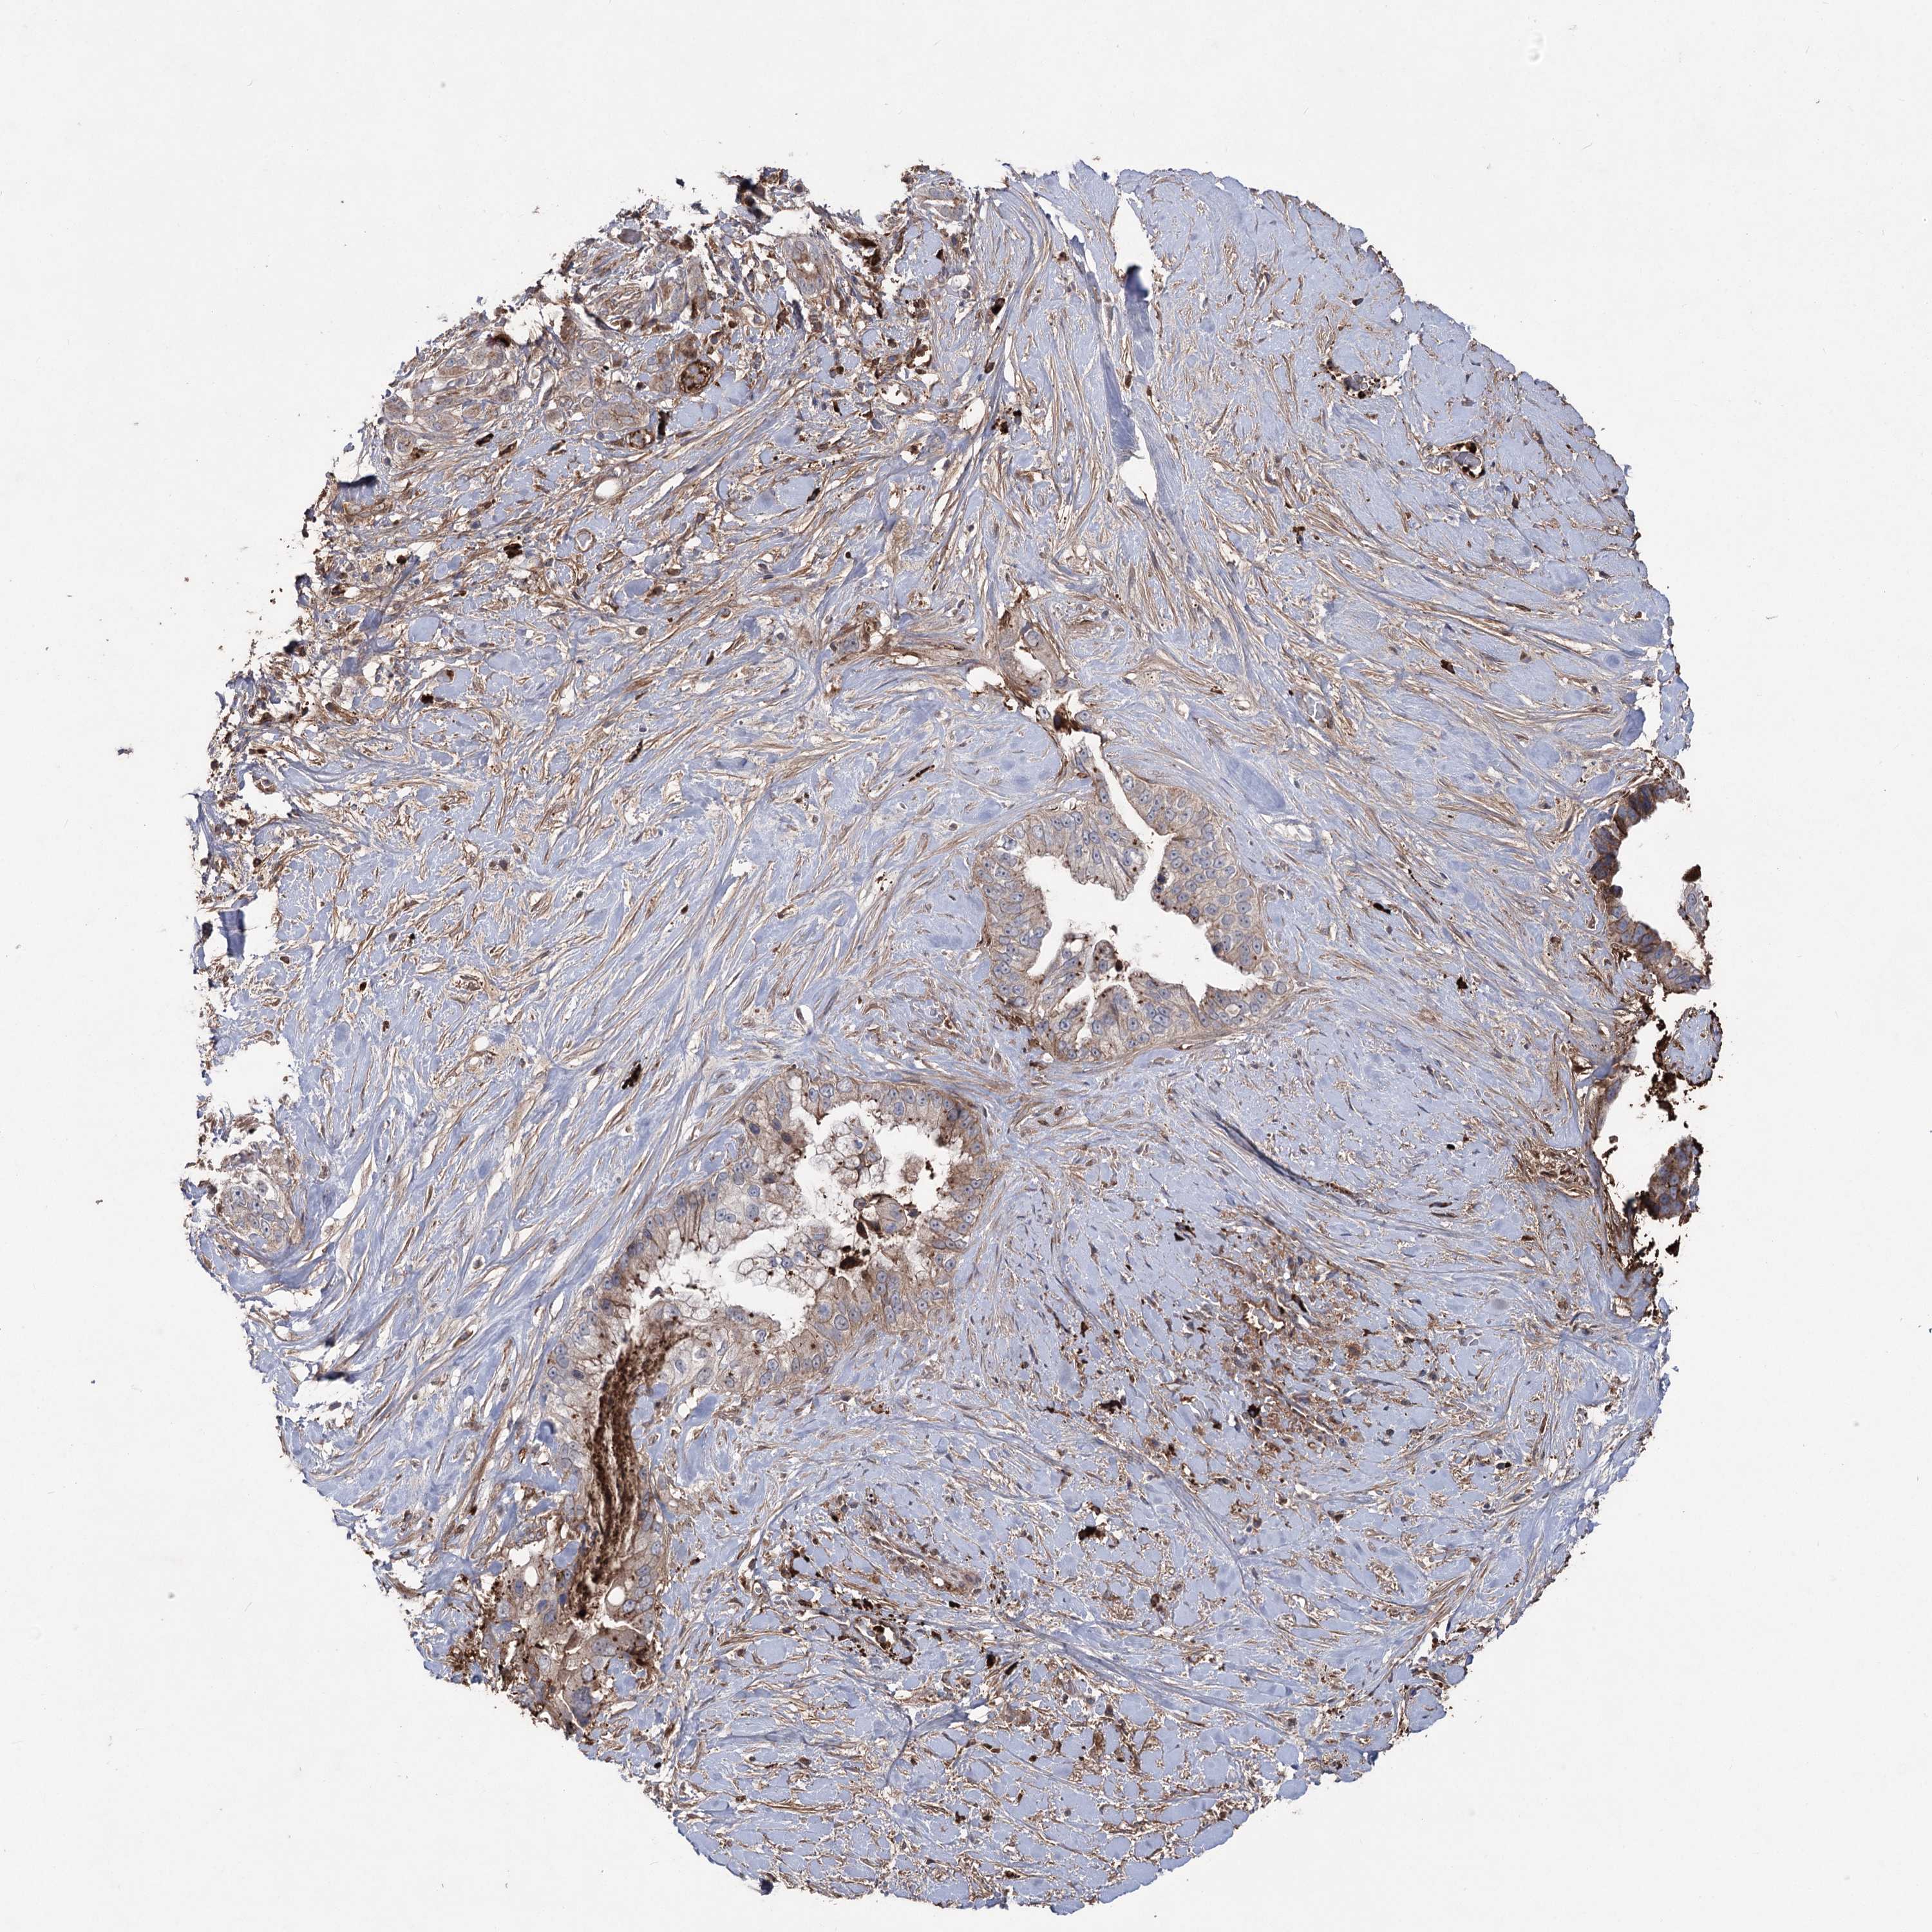

PANCREATIC CANCER - Protein expressioni

A mouse-over function shows sample information and annotation data. Click on an image to view it in a full screen mode. Samples can be filtered based on level of antibody staining by selecting one or several of the following categories: high, medium, low and not detected. The assay and annotation is described here.

Note that samples used for immunohistochemistry by the Human Protein Atlas do not correspond to samples in the TCGA dataset.

Antibody stainingi

Antibody staining in the annotated cell types in the current human tissue is reported as not detected, low, medium, or high, based on conventional immunohistochemistry profiling in selected tissues. This score is based on the combination of the staining intensity and fraction of stained cells.

Each image is clickable and will lead to virtual microscopy that enables deeper exploration of all samples and also displays staining intensity scores, fraction scores and subcellular localization as well as patient and tissue information for each sample.

Antibody HPA038504

Staining

High

Medium

Low

Not detected

Intensity

Strong

Moderate

Weak

Negative

Quantity

>75%

75%-25%

<25%

None

Location

Nuclear

Cytoplasmic/membranous

Cytoplasmic/membranous,nuclear

Adenocarcinoma, NOS